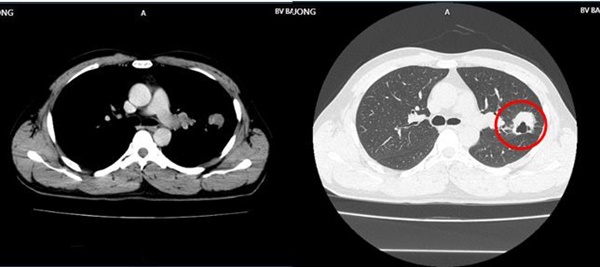

Hình ảnh khối u thùy trên phổi trái, kích thước 30x32mm (vòng tròn màu đỏ), vài nốt mờ rải rác màng phổi 2 bên của bệnh nhân. Ảnh: BVCC

Hình ảnh CT ngực trước điều trị cho thấy u thùy trên phổi trái kích thước 30x32mm, vài nốt mờ rải rác màng phổi 2 bên. Hình ảnh CT ngực sau 9 tháng thể hiện khối u phổi phải tiếp tục giảm kích thước 16x19mm, không còn hạch rốn phổi. Hạch trung thất không còn, tổn thương di căn não đơn ổ biến mất, chất chỉ điểm khối u CEA, Cyfra 21-1 giảm về giới hạn bình thường.